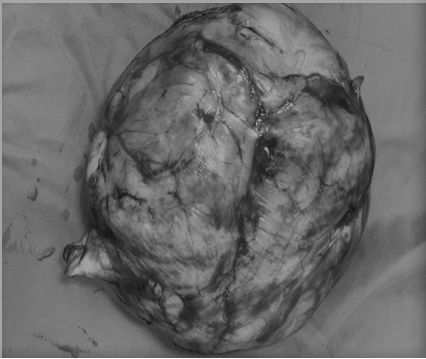

Qua thăm khám, các y, bác sĩ của bệnh viện đánh giá thai phụ có khối u mềm, kích thước lớn khoảng 18 x 12 cm chèn ép gây khó khăn trong việc xác định cổ tử cung. Kết quả siêu âm ghi nhận 1 thai ngôi đầu đang phát triển trong buồng tử cung, mặt trước thân tử cung đoạn eo có khối u xơ kích thước lớn. Bên cạnh đó, khối u xơ tử cung lớn ở đoạn dưới tạo thành khối u tiền đạo, gây cản trở đường ra của thai qua ngã âm đạo.

Sau đó, các y, bác sĩ củaệnh viện Đa khoa Trung ương Quảng Nam đã tiến hành phẫu thuật cho sản phụ P. mổ bắt con thành công, đồng thời loại bỏ được khối u xơ kích thước lớn. Hiện tại sức khỏe của sản phụ này và cháu bé ổn định.